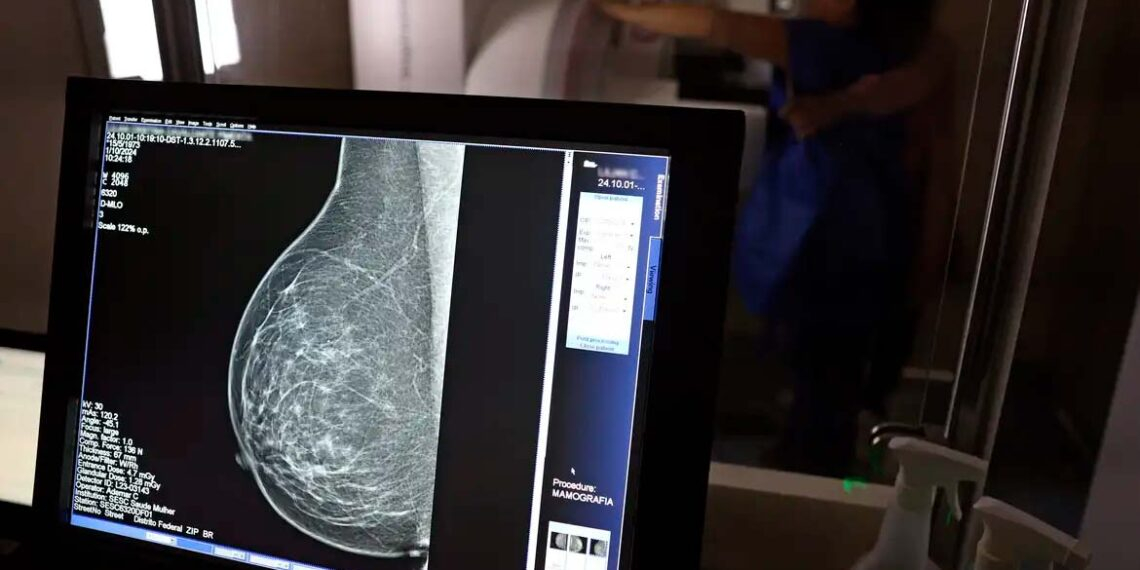

Como parte do Outubro Rosa, o Colégio Brasileiro de Radiologia e Diagnóstico por Imagem (CBR) lançou a campanha Radiologia Solidária, com o objetivo de oferecer exames gratuitos para mulheres de baixa renda em todo o Brasil. Mais de 50 clínicas de imagem e instituições de saúde participarão da iniciativa até dezembro, divididas em três categorias: ouro, prata e bronze, conforme o número e tipo de exames a serem disponibilizados.

A categoria ouro conta com 21 clínicas, que disponibilizarão mais de 50 mamografias e/ou tomossínteses, além de mais de 20 ultrassonografias e/ou biópsias de mama. A prata inclui sete clínicas, oferecendo de 20 a 50 mamografias e até 20 ultrassonografias. Na categoria bronze, 22 clínicas oferecem até 20 mamografias e 10 ultrassonografias.